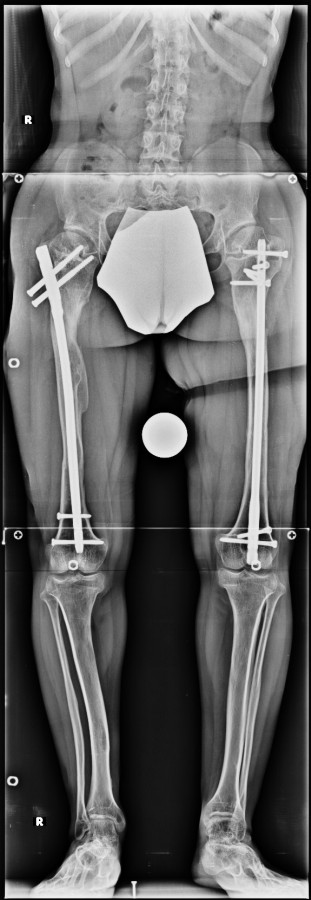

Cücelerde boy kısalığı için uyguladığımız boy uzatma programında sadece boy uzatmayı değil aynı zamanda ayak bileği, diz , kalça ve el bileği deformitelerinin düzeltilmesini ve lomber hiperlordozun azaltılmasını amaçlamaktayız. Lomber hiperlordozun azaltılması yetişkin yaşlarda spinal stenoz riskini azaltır. Başvuru anındaki yaşına göre iki tip tedavi stratejisi bulunmaktadır.

6-8 yaşları arasında Femur (uyluk) ve tibiada (bacak) toplam 10cm boy uzatma (6cm femur ve 4 cm tibia) Parantez bacak deformitesinin düzeltilmesi Ortalama eksternal fiksasyon tedavi süresi = 5 ay İkinci, üçüncü ve dördüncü boy uzatmalar Yetişkin stratejisinde (aşağıda) olduğu gibi Alt uzuvlarda (Diz üstü ve altı dahil) toplam 30-35 cm boy uzatma Üst uzuvlarda toplam 10-12 cm boy uzatma

14 ve 16 yaşlar arasında her iki femurda toplam 10-12 cm boy uzatma her iki kalçanın fleksiyon deformitesinin düzeltilmesi (bu lomber hiperlordozu düzeltir) her iki kalçanın varus deformitesini düzeltme ortalama eksternal fiksasyon tedavi süresi = 10-12 ay

12-14 yaşları arasında Her iki tibiada toplam 10-15cm boy uzatma (iki seviyeli uzatma) Proksimal tibianın varus deformitesini proksimal osteotomi ile düzeltilmesi Distal tibianın varus deformitesi distal osteotomi ile düzeltmesi Distal tibianın varus deformitesi distal osteotomi ile düzeltmesi Boy uzatmanın sonunda lateral kollateral ligamentin gerilmesi Ortalama eksternal fiksasyon tedavi süresi = 8-10 ay